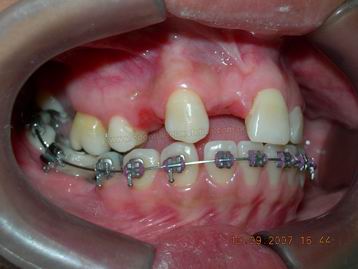

VISTA LATERAL DURANTE FASE DE ALINHAMENTO E NIVELAMENTO INFERIOR |

VISTA LATERAL DURANTE FASE DE ALINHAMENTO E NIVELAMENTO BIMAXILAR |

FASE INICIAL DO TRATAMENTO ORTODÕNTICO COM FIO RETANGULAR TERMOATIVÁVEL

FASE INICIAL DO TRATAMENTO ORTODÕNTICO (vista lateral esquerda) |

FASE INICIAL DO TRATAMENTO ORTODÕNTICO (vista lateral direita) ANTES DA ABERTURA DO ESPAÇO PARA O INCISIVO LATERAL DIREITO